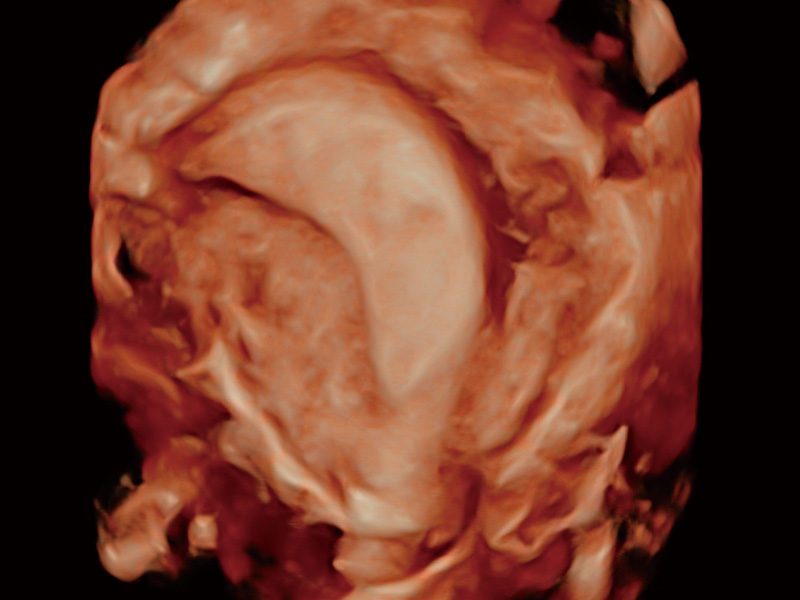

“生育问题”即关系民族复兴,也关系亿万家庭的幸福。随着婚育年龄推迟、社会压力增加等因素,越来越多人群也面临着“生不出、生不好”的问题。辅助生殖作为治疗不孕不育最有效的方法之一,也逐渐成为育儿新希望。而超声检查能为生殖需求人群的初诊评估提供宝贵的信息。 P20 Elite是玖鼎集团匠心打造的一款生殖应用型彩超。她继承玖鼎集团高端极光平台,突破性地将多款新型芯片及硬件模块进行整合,均衡了高端系统性能与小巧灵动机身。P20 Elite卓越的图像质量搭载专科探头,旨在为您提供全面的辅助生殖解决方案。

P20 Elite配备了丰富的生殖探头群和临床应用功能,在卵泡监测、穿刺取卵、胚胎移植、妊娠确认等领域,为生殖需求人群提供了新的临床机会,重新定义高端超声如何应用于生殖健康检查。